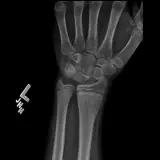

Over 2,100 interactive radiology cases, curated by radiologists for your level of training. Scroll, window, and view cases full screen — just like on PACS. Click linked findings in each writeup to jump straight to them on the image. Cases include sample reports, a focused discussion section, original illustrations, and videos.

PACSで期待されるツールを完備した完全インタラクティブな症例 — スクロール、ウィンドウ調整、ズーム、パン、計測、ROI、フルスクリーンモード。

重要な所見を症例画像上に直接ハイライトする豊富なアノテーション。症例解説内のリンクされた所見をクリックすると、スキャン上の正確な位置へジャンプできます。

職場のPACSステーションと同じようにスクロール、パン、ウィンドウ調整、ズームが可能

アノテーション付きの画像所見とイラストで効率的に学習